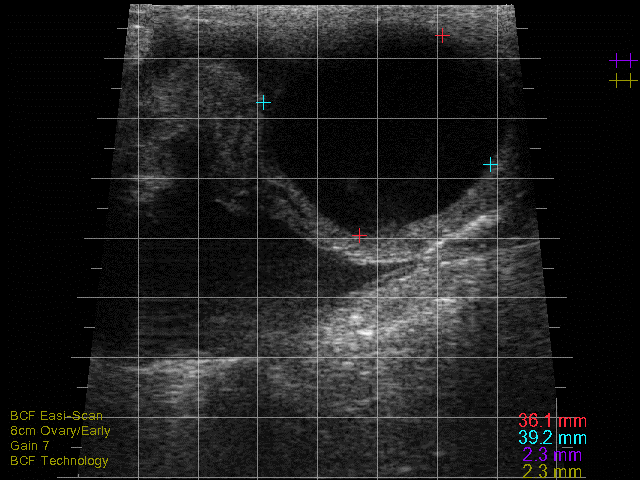

Detection of a CL is a useful finding for a practitioner as it indicates that a cow is cyclic. CLs typically appear as a solid, moderately echogenic (grey-like) structures on the ovary with a round appearance2. However, it is common for CLs to have an irregular or lobulated shape, particularly if there is an ovulation point2. Many will develop with a central cavity and this is commonly seen in the first 10 days of the cycle with up to 30-50 per cent of CLs being cavitated2. CLs vary in size and structure depending on the stage of the cycle. In the early luteal phase (days one to five), the CL will appear as a small (~12-14mm), soft structure with a developing echogenic rim and often a cavity2. From the mid-luteal phase (days eight to 16), the CL is larger (20-25mm) more well-defined and often solid, although some cavities within CLs can persist throughout the cycle and even into pregnancy, with the vast majority filling in by 30 days of gestation2.